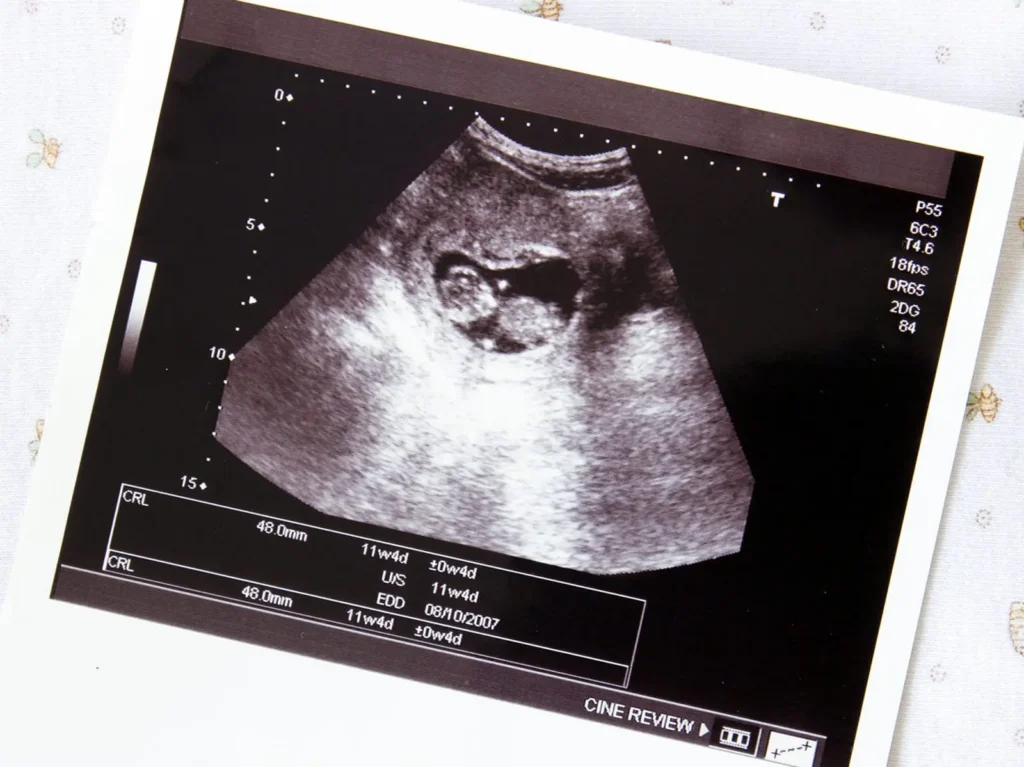

- Ultraschalluntersuchung